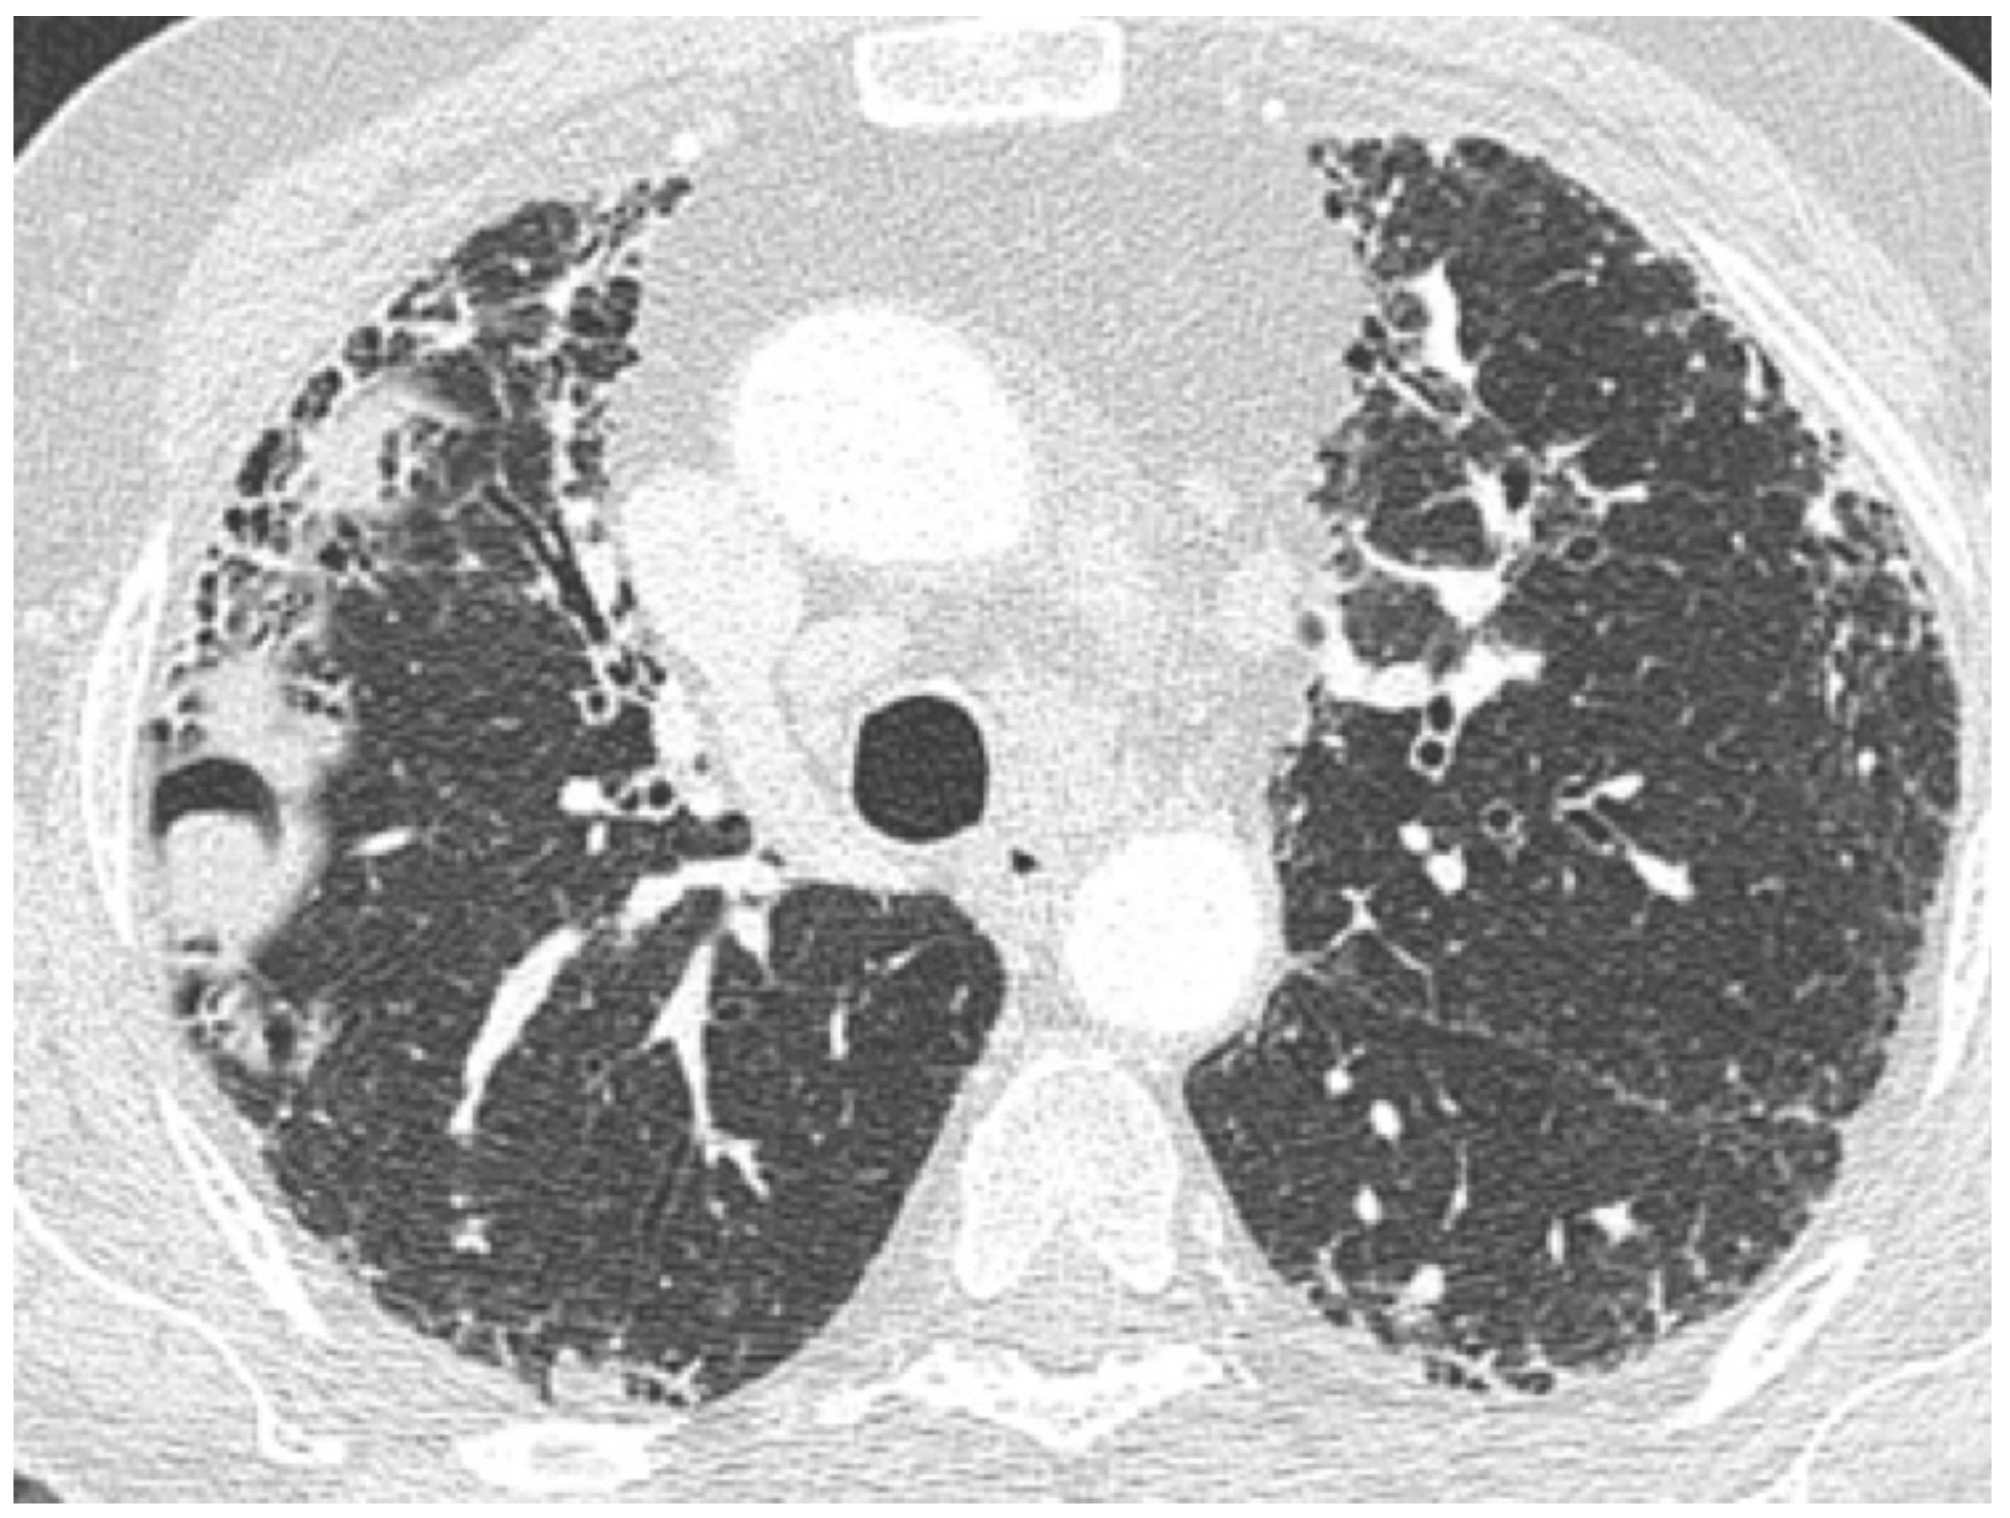

| Chronic | Lung cancer | Ill-defined rounded lesion, mimicking air space consolidation/nodular lesion developing within peripheral and basal honeycombing areas. Ground glass opacity in fibrosis area (mucinous bronchioloalveolar carcinoma). | |